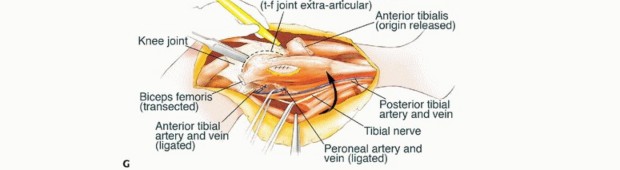

الاستئصال من النوع الثاني (Type II Resection):

- الإشارة: يُستخدم لعلاج الأورام الغرنية عالية الدرجة، والتي عادةً ما يكون لديها تدمير قشري كبير مع امتداد خارج العظم.

- الإجراء: يشمل إزالة الشظية القريبة والمفصل الظنبوبي الشظوي، والحجرات العضلية الأمامية والجانبية، والعصب الشظوي، والشريان الظنبوبي الأمامي بشكل كامل. يتطلب هذا النوع ربط الشريان الظنبوبي الأمامي وقد يتطلب أيضًا التضحية بالشريان الشظوي.

- الحفاظ: لا يتم الحفاظ على العصب الشظوي والشريان الظنبوبي الأمامي.

يوضح الجدول التالي الهياكل التشريحية التي يتم إزالتها مع أنواع الاستئصال المختلفة للشظية القريبة:

| نوع الجراحة | موقع ارتباط الرباط الجانبي الوحشي | الشريان الظنبوبي الأمامي | العصب الشظوي |

|---|---|---|---|

| الكشط | سليم | سليم | سليم |

| استئصال من النوع الأول | مُزال | سليم | سليم |

| استئصال من النوع الثاني | مُزال | مُزال | مُزال |